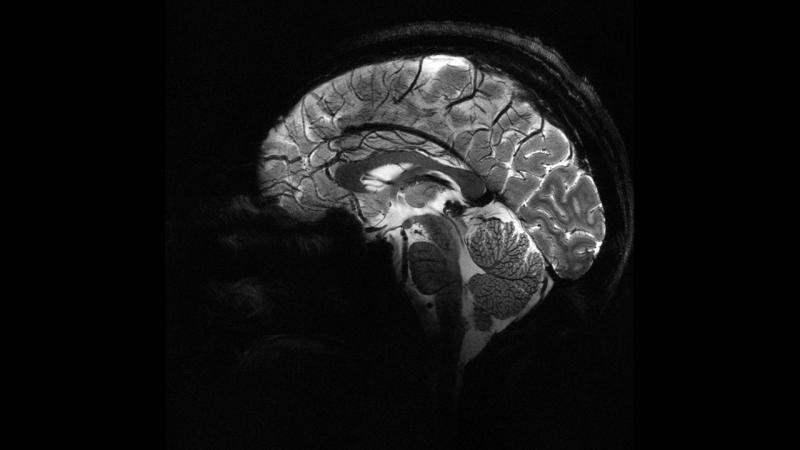

Iseult Projesi Başkanı ve CEA Araştırma Direktörü Nicolas Boulant, yaptığı açıklamada, verilerin daha yüksek kalitede elde edilebilmesi için araştırmanın birkaç yıl daha devam edeceğini belirterek, hedeflerinin 2026-2030’a kadar nörodejeneratif hastalıkların yanı sıra şizofreni ve bipolar bozukluğu gibi psikiyatri alanındaki birçok hastalığı araştırmak olduğunu ifade etti.

Iseult MRI cihazı ile elde edilen ultra detaylı anatomik bilgilerin, Alzaymır ve Parkinson gibi hastalıkların teşhisinde yardımcı olması bekleniyor.